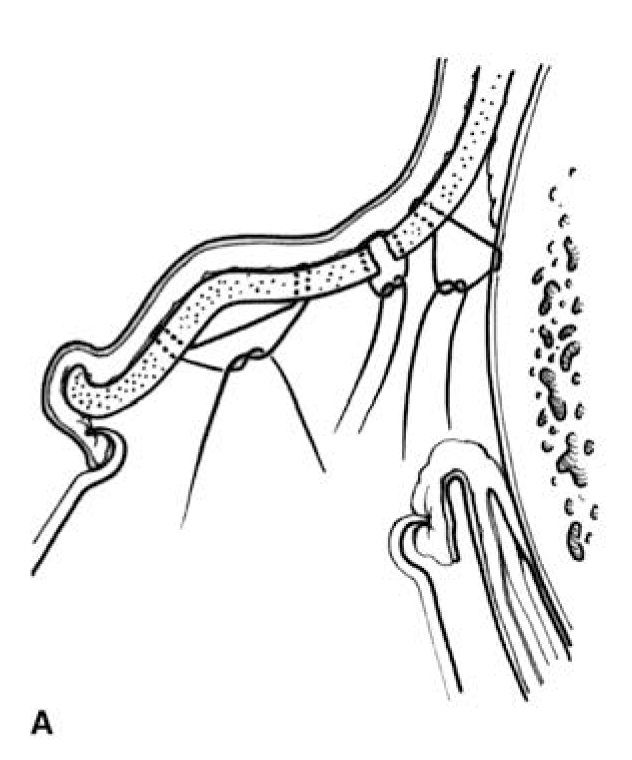

FIGURE 49.5.Otoplasty technique: The combination of a Mustarde scapha-conchal suture, conchal resection with primary closure, and a Furnas conchal-mastoid suture. Note that the conchal closure is at the junction of the floor and posterior wall of the concha. A. Sutures placed. B. Sutures tightened to create the desired contour. C. Same sutures as seen through the retroauricular incision. (Reproduced with permission of Charles H. Thorne, MD. Copyright Charles H. Thorne, MD.)

of the deformity and in part on the surgeon’s personal preferences.6 This author’s preferred technique involves Mustarde sutures to recreate the antihelix and set back the upper and middle thirds of the ear. The abrasion techniques are unreliable, uncontrollable, and unnecessary and may result in sharp edges or an overdone appearance. It should be noted that the antihelix is not straight; rather it curves forward superiorly, to almost parallel the inferior crus. To create an antihelix of the correct contour, the sutures are not placed parallel to each other but rather placed like spokes of a wheel, with the center of the wheel being the top of the tragus. If the sutures are placed parallel to each other, the antihelix will be excessively straight. In the conchal region, the author most commonly uses both a conchal resection and Furnas conchal-mastoid sutures as shown in Figure 49.5. The combination allows the resection to be small (1 to 2 mm), minimizing iatrogenic deformity. When conchal excision is used alone, a deformity of the posterior wall of the concha may result. When Furnas sutures are used alone, the correction may be inadequate, the patient may have pain, the external auditory canal can be narrowed, and the depth of the retroauricular sulcus is decreased. As mentioned above, earlobe repositioning is the most difficult part of the procedure. The Webster technique of repositioning the helical tail has not been effective in the author’s hands for correction of earlobe prominence. Rather, the Webster technique appears to reposition the ear just above the earlobe, exaggerating the earlobe prominence